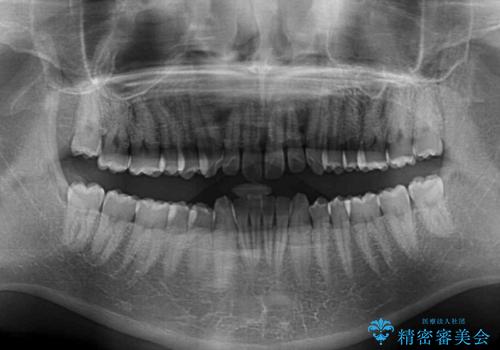

- 前歯のデコボコや隙間と深い咬み合わせ(ディープバイト)を気にして来院された患者様です。

インビザラインによる上下歯列の側方拡大と後方移動、IPR(歯と歯の間を削る)にるスペースの獲得により、デコボコとディープバイトを改善することとしました。

後方移動に際し、上下の親知らずは4本全て抜歯することとしました。